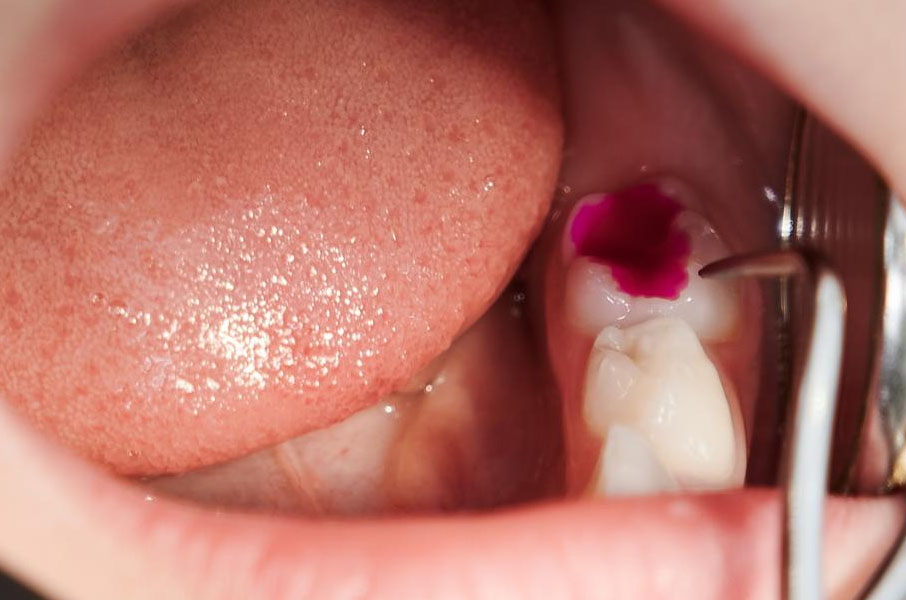

Dental fillings Chandler are a material used to repair and fix a tooth that has been damaged by decay or injury. When your tooth develops a cavity, the decayed part of the tooth is removed, and a dental filling is placed in the hole to restore the tooth’s structure. Dental fillings solve problems like preventing further decay, stopping tooth pain, and protecting the tooth from future damage.

3. Once the area is numb, Dr. Behbahani will carefully remove the tooth decay.

4. The filling material will be put into the cavity and shaped to match the tooth natural contours.

5. The filling is then hardened using a special light.